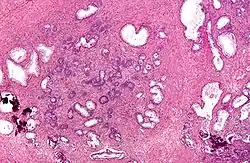

Benign hyperplasia prostate, evidence of bladder neck obstruction.

Both the glandular epithelial cells and the stromal cells (including muscular fibers) undergo hyperplasia in BPH.[2] Most sources agree that of the two tissues, stromal hyperplasia predominates, but the exact ratio of the two is unclear.[47]: 694

Anatomically the median and lateral lobes are usually enlarged, due to their highly glandular composition. The anterior lobe has little in the way of glandular tissue and is seldom enlarged. (Carcinoma of the prostate typically occurs in the posterior lobe – hence the ability to discern an irregular outline per rectal examination). The earliest microscopic signs of BPH usually begin between the age of 30 and 50 years old in the PUG, which is posterior to the proximal urethra.[47]: 694  In BPH, the majority of growth occurs in the transition zone (TZ) of the prostate.[47]: 694  In addition to these two classic areas, the peripheral zone (PZ) is also involved to a lesser extent.[47]: 695  Prostatic cancer typically occurs in the PZ. However, BPH nodules, usually from the TZ are often biopsied anyway to rule out cancer in the TZ.[47]: 695  BPH can be a progressive growth that in rare instances leads to exceptional enlargement.[48] In some males, the prostate enlargement exceeds 200 to 500 grams.[48] This condition has been defined as giant prostatic hyperplasia (GPH).[48]